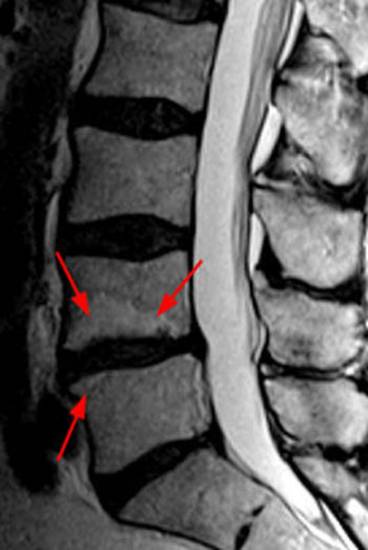

На снимке МРТ представлен поясничный остеохондроз, стрелками обозначен пораженный диск с формированием спондилодисцита